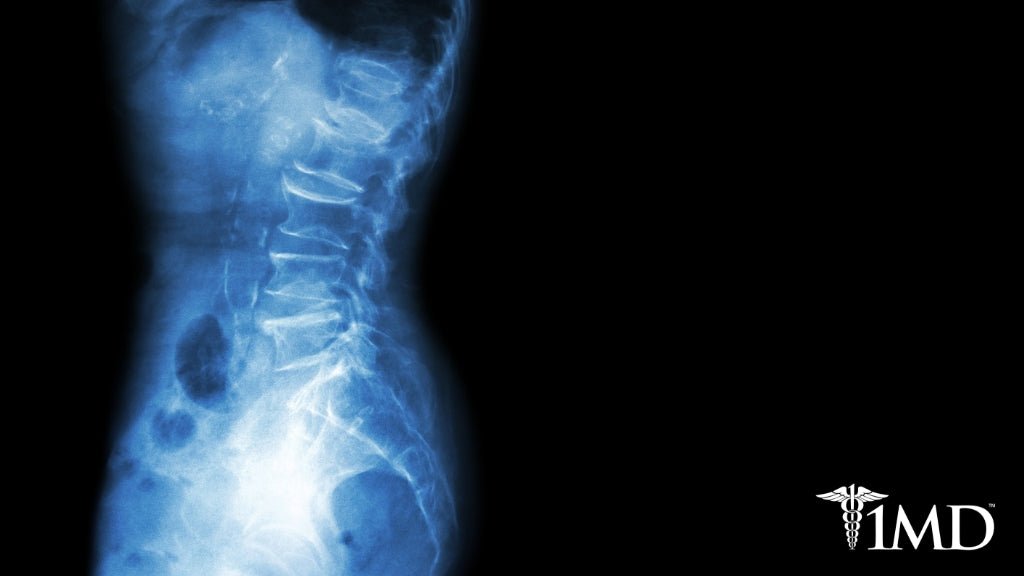

With the stress of daily life and all of our responsibilities, back pain has generally been accepted to be a part of everyday life. While back pain can result from a pulled muscle or overexertion, there may be a deeper problem. Ankylosing spondylitis is a condition that affects millions and is classified as a form of arthritis that affects your spine.

Unlike other forms of arthritis, like osteoarthritis, ankylosing spondylitis can strike at any age. The spine is the most common part of the body diagnosed with this condition, but you may also notice pain in your hips, shoulders, hands, and feet. Because of the degree with which symptoms and pain can vary among individuals, it’s essential to understand how to identify ankylosing spondylitis.

Ankylosing spondylitis is a chronic and progressive condition, which means it gets worse as time goes by. The pain may come and go, but if it radiates up your spine and gets worse with each painful episode, you likely have identified the culprit.

It’s important to seek diagnosis and treatment right away; otherwise, the vertebrae in your spine can fuse, causing curving of the spine and a hunchbacked appearance.

Without proper treatment, ankylosing spondylitis can cause your spinal vertebrae to fuse, putting you at an increased risk for fractures and additional pain. There is no cure that can reverse the condition, but there are preventive treatments that can delay its progression.